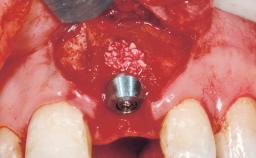

A 29-year-old female patient presented for treatment to replace the upper left central incisor tooth with an implant- supported restoration. The tooth had been intermittently symptomatic for the previous 12 months. The tooth had originally suffered trauma about 15 years previously. Several endodontic treatments had been performed, including an apicectomy procedure to retain the tooth. The patient was healthy and a non-smoker. She had reasonable expectations in regard to esthetic outcomes and the risk of marginal tissue recession following treatment. At medium smile, the gingival margins of the upper teeth were visible, with a display of 3 to 4 mm of the gingival margins. Gingival recession of tooth 21 and a discrepancy in the gingival levels between teeth 11 and 21 was observable during normal speech and smile.

| Placement Protocol | Immediate implant placement |

| Tooth Site | Maxillary incisor or canine |

| Socket Morphology | Single-root socket |

| Socket Integrity | Damage to one or more bone walls |